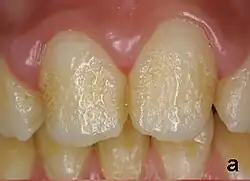

Amelogenesis imperfecta (ang. amelogenesis imperfecta, AI) – grupa uwarunkowanych genetycznie zaburzeń rozwoju szkliwa zębów. Zęby chorych z amelogenesis imperfecta są małe, przebarwione, mają nieprawidłowo ukształtowaną powierzchnię, są podatne na uszkodzenia i przedwcześnie wypadają. Choroba może dotyczyć zarówno uzębienia mlecznego, jak i stałego. Wyróżniono wiele typów i klasyfikacji klinicznych schorzenia.